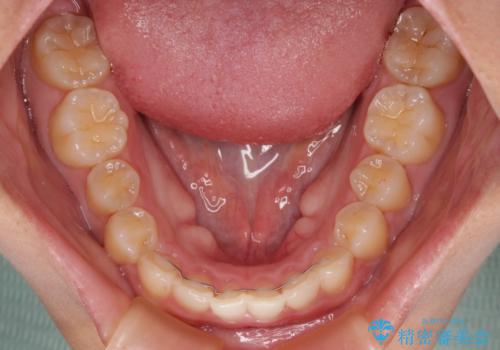

- 前歯の突出感を気にして来院された患者様です。

奥歯の咬み合わせは理想的な咬合に近く、インビザラインでも十分に対応できる歯列でした。

舌の突出癖を改善するためのトレーニングを行いつつ、上下歯列全体を後方に移動させ、更にはIPR(歯と歯の間を削る)によりスペースを獲得することで、口元の突出感を改善することとしました。